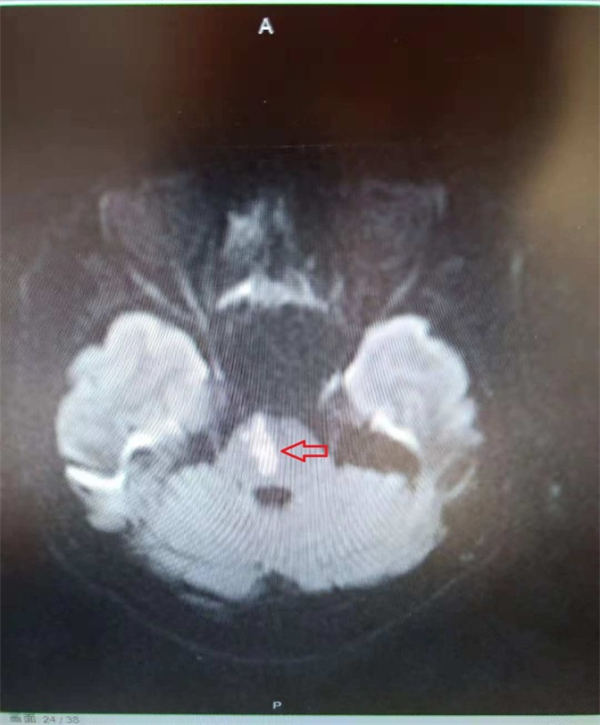

隔天上午,老杜两口子就挂了北京燕化医院肿瘤微创介入科陈力强主任的号,给老杜做了详细的体检之后,看着老杜拿过来的CT片子,陈主任说:“还好您这次脑梗塞的范围不大(上图红色箭头所示),所以后遗症不是很重,恢复也快。”